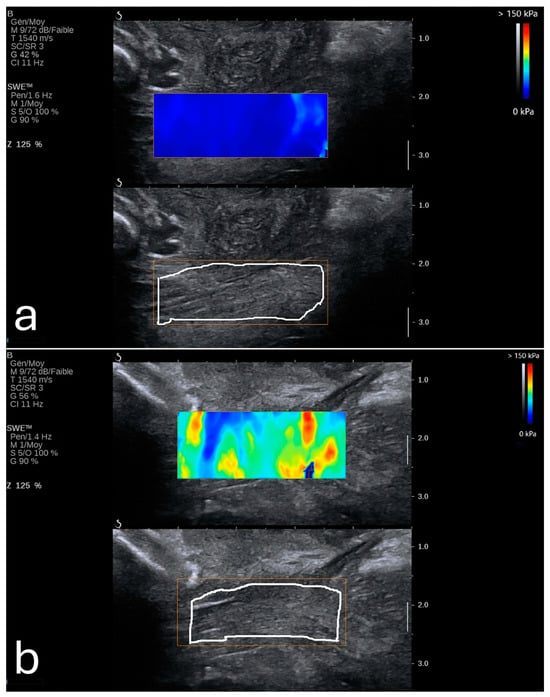

Sonoelastography offers a unique window into fetal development by providing quantitative insights into tissue properties and markers for identifying developmental progress and complications. By measuring the elastic properties of key organs such as the lungs, liver, and brain, clinicians could potentially evaluate organ maturity, detect potential anomalies, and make informed decisions regarding perinatal care [,,,,,,,,]. Figure 4 shows an example of a normal lung and liver in a fetus.

Figure 4. Normal shear wave elastography images of fetal lung (a) and liver (b) with elasticity values of 4.43 kPa and 5.09 kPa, respectively. Image adapted from Liu et al. [] under a Creative Commons Attribution 4.0 International License. Changes were made to resize and adjust the images.